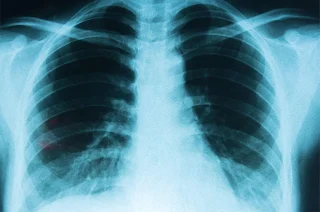

13 mayo 2025.- A lo largo de la última década se ha observado un notable incremento en el interés por el trasplante pulmonar doble como intervención para pacientes con cánceres avanzados, especialmente en aquellos casos en los que las terapias convencionales han ofrecido resultados limitados. Esta intervención, que originalmente surgió en el campo de las enfermedades pulmonares crónicas, está siendo rediseñada y adaptada para abordar formas agresivas y de difícil tratamiento de cáncer, en un intento por mejorar la calidad y la extensión de vida en pacientes seleccionados .

El trasplante pulmonar doble tradicionalmente se ha reservado para enfermedades como la fibrosis pulmonar idiopática, la EPOC o la fibrosis quística. Sin embargo, investigaciones recientes apuntan a que, para ciertos cánceres de pulmón y en situaciones con tumores localmente avanzados, la sustitución completa del pulmón mediante un trasplante doble puede eliminar de manera efectiva un microambiente tumoral favorable al crecimiento neoplásico. Estas estrategias están siendo evaluadas en centros especializados, donde se combinan criterios estrictos de selección de pacientes y soluciones innovadoras en cirugía oncológica .